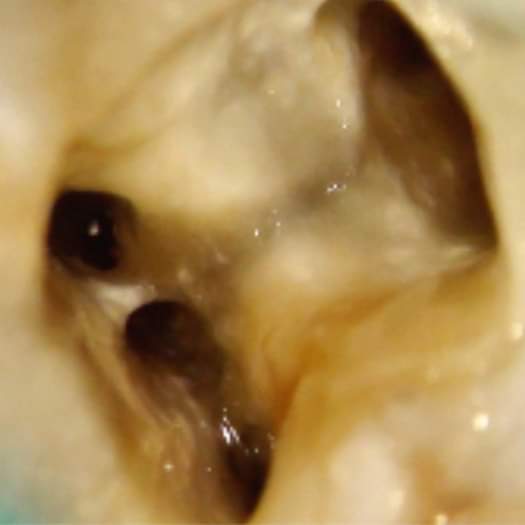

Middle Mesial Canal

في وقت احنا كنا نحاول بجهد نلقى MB2 طلعت ناس اكتشفت انو فيه mmc

يجي عالم vertucci ويصف انو فيه كانال بين

ال MB and ML

بالlower first molar

وكانت صعب تلقى هذي الCanal خصوصاً هي راح تكون موجودة بال isthmus area فتحتاج تشيل وتنظف ال isthmus زين

ال dental microscope

اللي ممكن ال Dentist يشوف كل شي داخل الكانال

يقول تحتاج تستخدم ميكروسكوب وتستخدم ultrasonic tip وتسوي troughing بين ال two main mesial canal ومقدار 2mm تنزل ياالله ممكن تلقاها وبالعادة تلقاها رايحة باتجاه ال ML اكثر ممكن من ال MB

نحتاج Magnification ونحتاج ultrasonic نبحث عنها بمنطقة ال isthmus وكذلك بداية اسوي irrigation وانظف واشيل

ال isthmus حتى تبين عندي